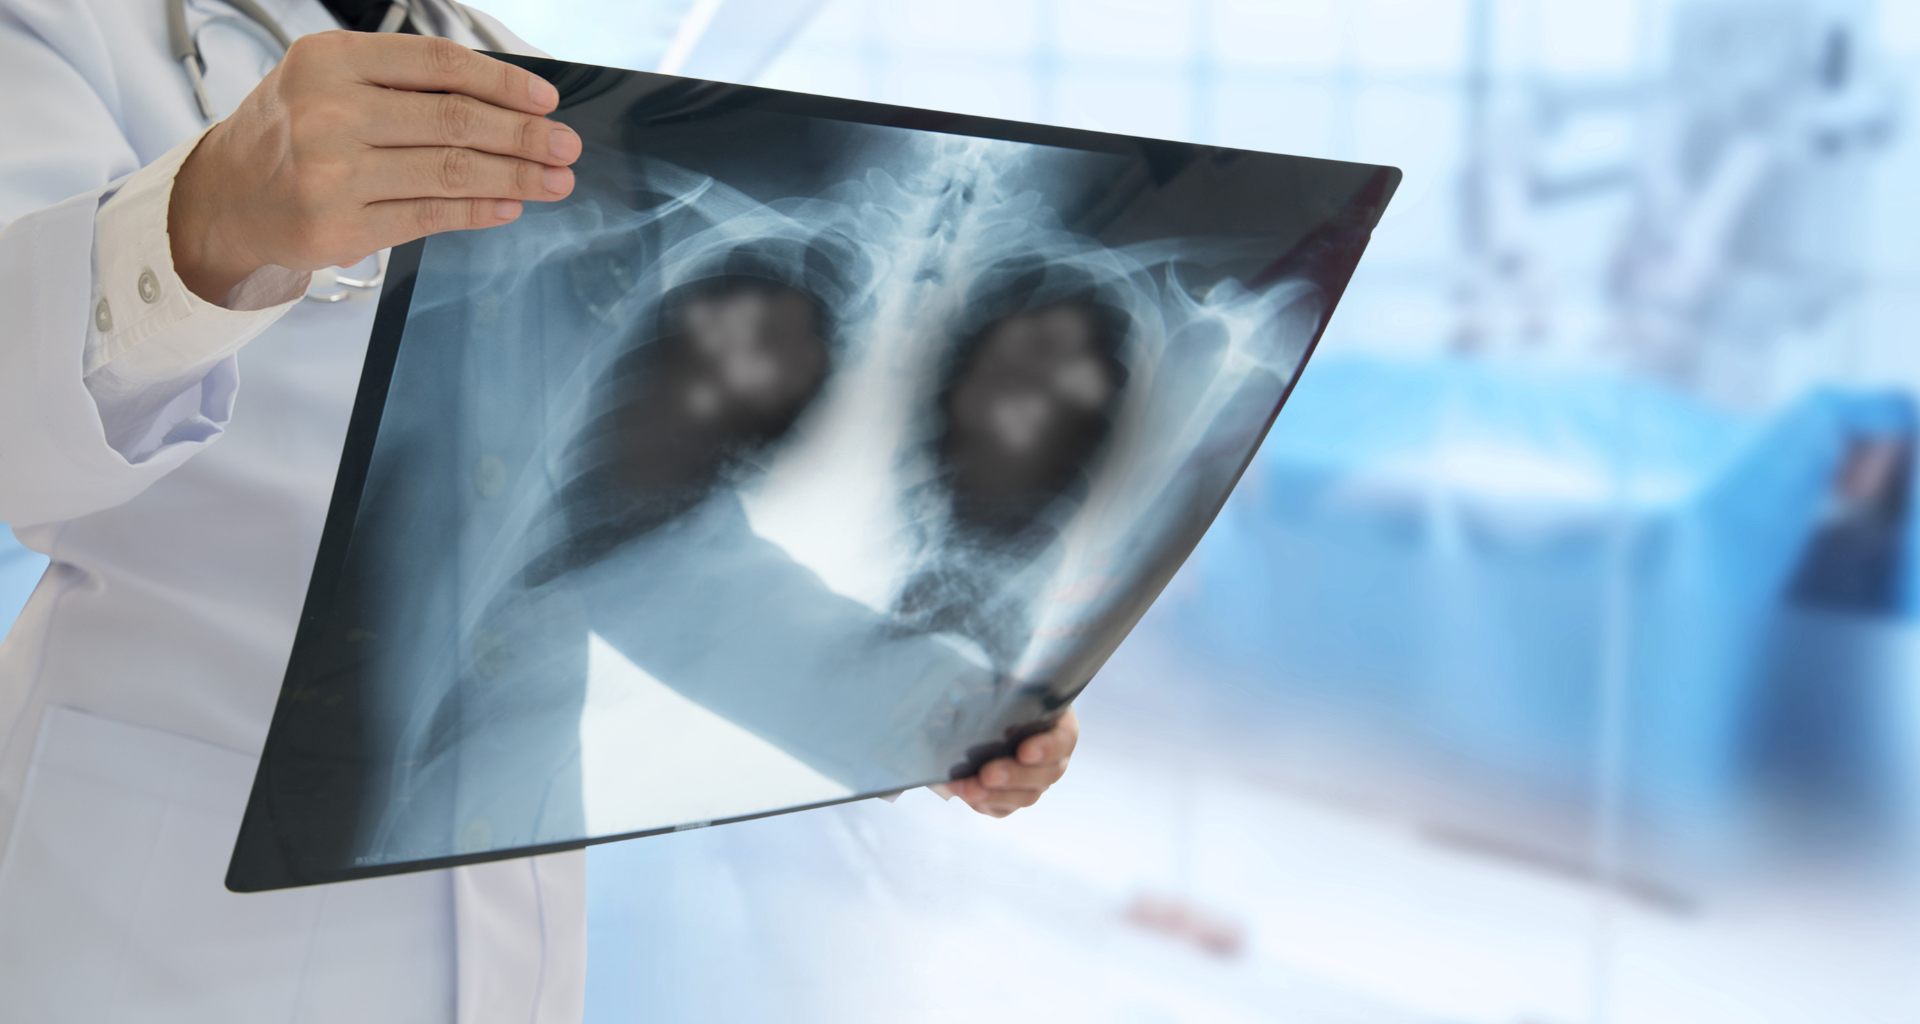

Per polmonite bilaterale si intende un’infezione (di natura virale, batterica o fungina) che colpisce entrambi i polmoni. La sua area di azione è soprattutto il tessuto interstiziale, quello che si trova tra un alveolo polmonare e l’altro.

Si tratta della parte più profonda dei polmoni, che nel giro di pochi giorni può portare il paziente ad un’insufficienza respiratoria grave. Per questo, per le patologie pregresse ed i suoi 88 anni di età, Bergoglio è considerato un paziente a rischio.

I sintomi più comuni sono febbre, brividi, tosse, mancanza di fiato, spossatezza e malessere generale. A volte può bastare l’auscultazione per diagnosticare una polmonite bilaterale. In altri casi, invece, possono essere richiesti esami strumentali, come TAC ed Eco toracica, o perfino esami del sangue. Quest’ultimo tipo di controllo è invece il meno frequente.

Senza dubbio, il modo più efficace per contrastare la polmonite bilaterale è la terapia farmacologica. La parte sicuramente più difficile è la scelta del giusto mix, che deve essere tarato sugli specifici patogeni che hanno causato l’infezione. In supporto, è quasi sempre necessaria l’ossigenoterapia.

Per la natura di questa complicazione, infatti, gli alvei polmonari si infiammano e si riempiono di liquido, rendendo difficoltoso lo scambio tra sangue e ossigeno. Nei casi più gravi, si può arrivare alla setticemia, che attraverso il flusso sanguigno può colpire il resto dell’organismo.